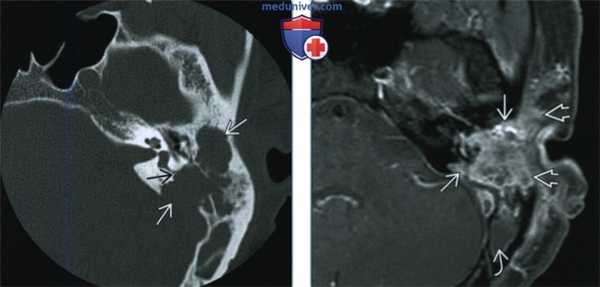

(Слева) КТ с контрастированием, корональный срез: у пятилетнего мальчика с хронической левосторонней отореей и кондуктивной тугоухостью определяется мягкотканное объемное образование в сочетании с деструкцией сосцевидного отростка теменной кости. Обратите внимание на четкие контуры дефекта кости и смещение слуховой косточки.

(Справа) КТ с контрастированием, аксиальный срез: у ребенка с медленно растущим объемным образованием в области правой щеки визуализируется объемное образование в виде мягкотканного компонента, расположенного в нижних отделах жевательного пространства. Обратите внимание на лизис наружных отделов ветви нижней челюсти.

(Слева) При аксиальной КТ в костном окне у двухлетней девочки с двухсторонней отореей определяются хорошо отграниченные деструктивные поражения (ЛКГ) сосцевидного отростка и чешуи височной кости с обеих сторон. Снижена пневматизация полости среднего уха с обеих сторон на фоне практически полной деструкции слуховых косточек. Агрессивная периостальная реакция, типичная для метастатической нейробластомы, в этом случае не выражена.

(Справа) При аксиальной МРТ Т1 С+ FS определяется ЛКГ с накоплением контраста и распространением в среднюю черепную ямку, кавернозный синус, внутренний слуховой канал. Слуховые косточки погружены в опухоль.